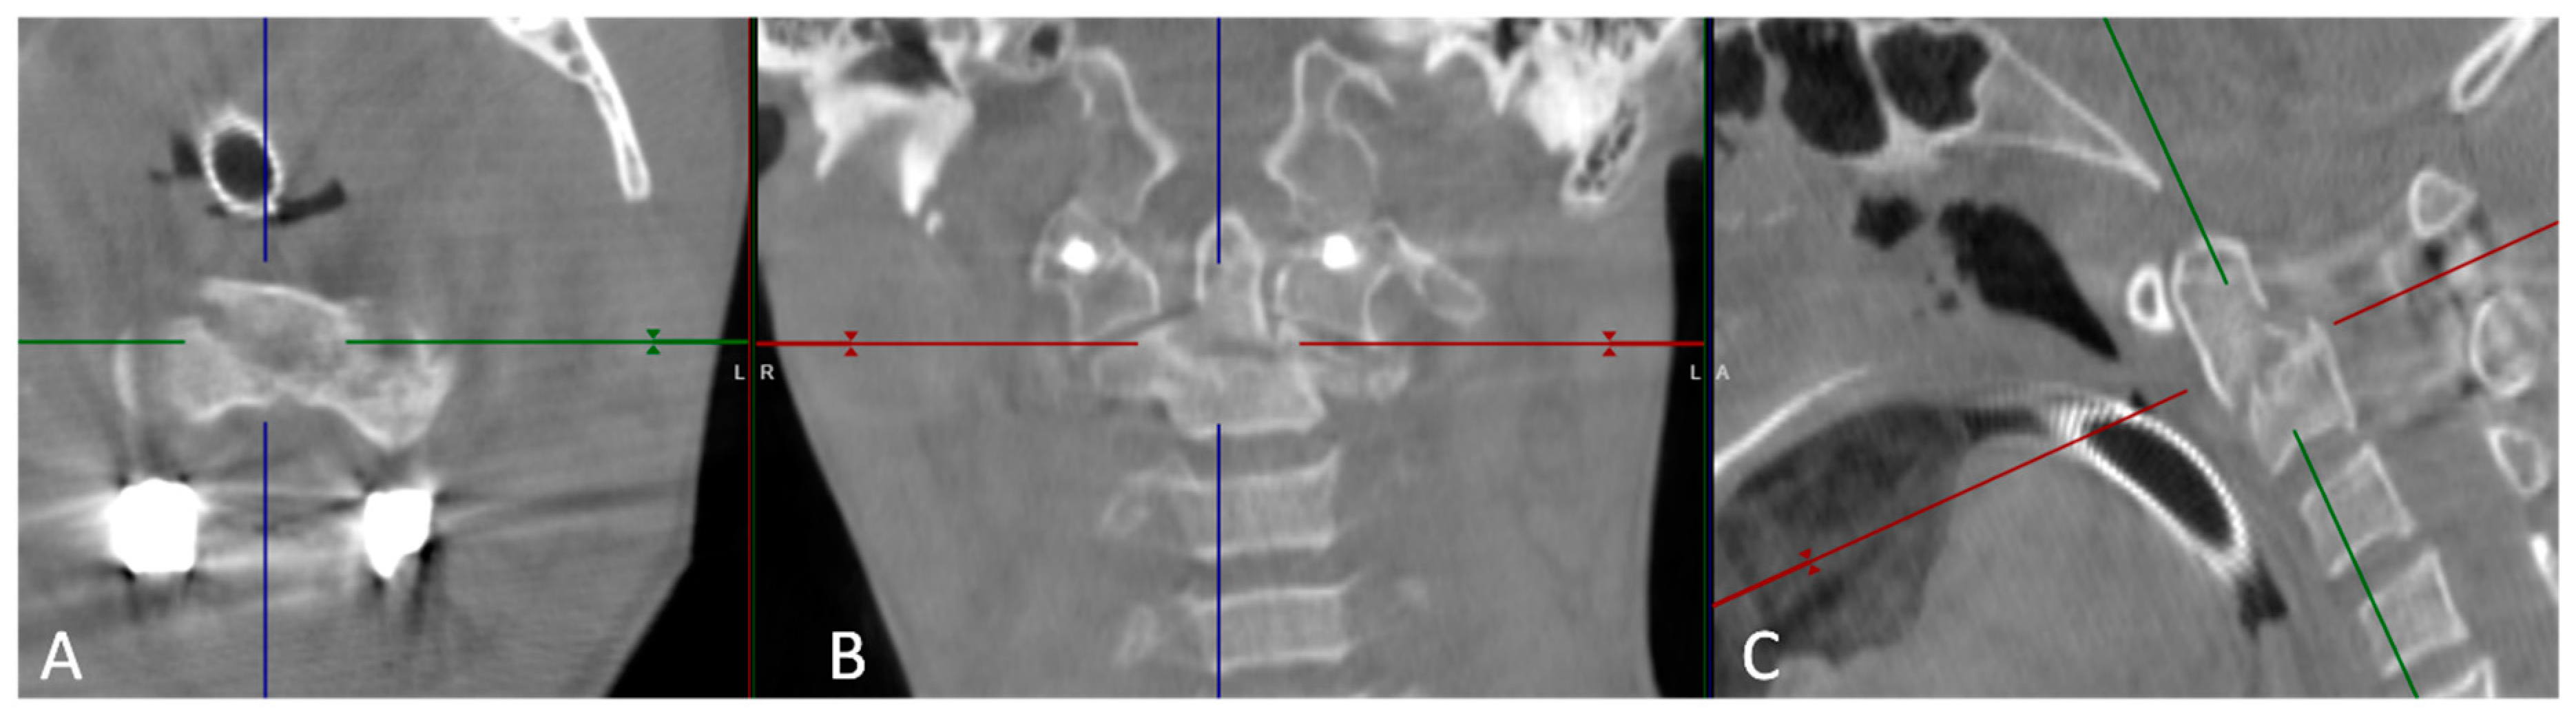

Figure 2. Functional cervical spine CT images: (A) Axial view; (B) Coronal view; (C) Sagittal view. The fracture is highlighted by the space between the 4 axes lines.